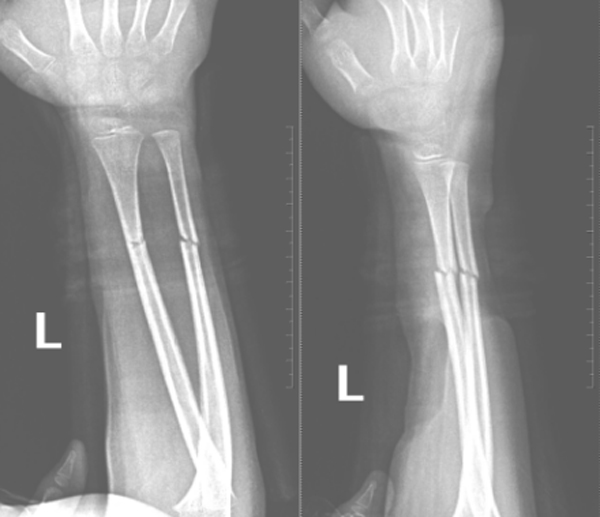

伤后34天复查

伤后48天复查

伤后58天复查

复位后,医护团队为家属详细指导护理事项,并制定系统复查计划。在随后数周的跟踪随访中,患儿骨折位置维持稳定,未出现移位。直至拆除夹板之日,其左前臂功能已基本恢复,骨骼愈合近乎完美。